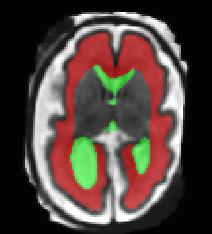

Limiting failures of machine learning systems is of paramount importance for safety-critical applications. In order to improve the robustness of machine learning systems, Distributionally Robust Optimization (DRO) has been proposed as a generalization of Empirical Risk Minimization (ERM). However, its use in deep learning has been severely restricted due to the relative inefficiency of the optimizers available for DRO in comparison to the wide-spread variants of Stochastic Gradient Descent (SGD) optimizers for ERM. We propose SGD with hardness weighted sampling, a principled and efficient optimization method for DRO in machine learning that is particularly suited in the context of deep learning. Similar to a hard example mining strategy in practice, the proposed algorithm is straightforward to implement and computationally as efficient as SGD-based optimizers used for deep learning, requiring minimal overhead computation. In contrast to typical ad hoc hard mining approaches, we prove the convergence of our DRO algorithm for over-parameterized deep learning networks with ReLU activation and a finite number of layers and parameters. Our experiments on fetal brain 3D MRI segmentation and brain tumor segmentation in MRI demonstrate the feasibility and the usefulness of our approach. Using our hardness weighted sampling for training a state-of-the-art deep learning pipeline leads to improved robustness to anatomical variabilities in automatic fetal brain 3D MRI segmentation using deep learning and to improved robustness to the image protocol variations in brain tumor segmentation. Our code is available at https://github.com/LucasFidon/HardnessWeightedSampler.